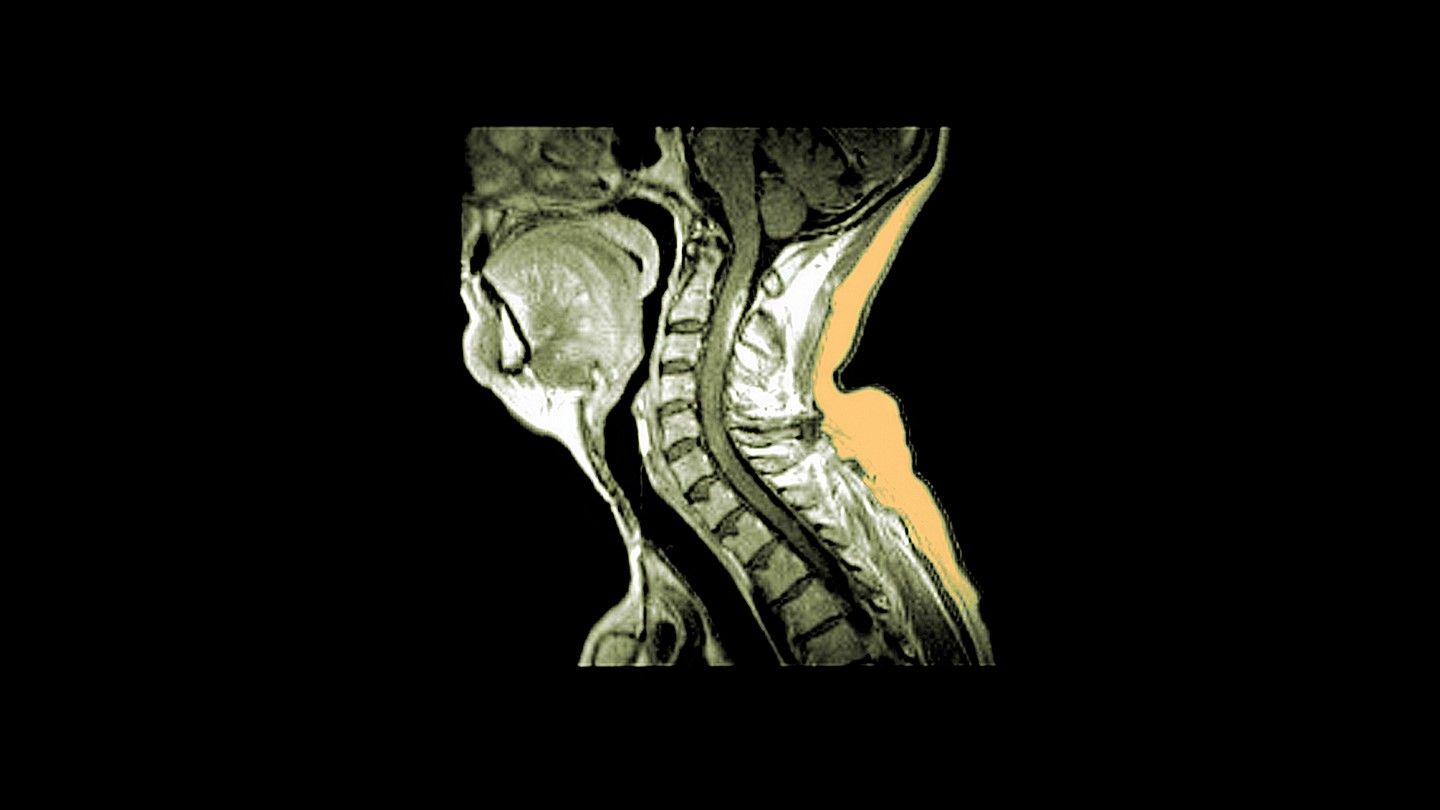

Când scleroza multiplă atacă măduva spinării

Leziunile măduvei spinării sunt mai frecvent observate în formele progresive de scleroză multiplă și pot duce la un risc crescut de dizabilitate.

Dar creierul nu este singura zonă în care se pot dezvolta leziuni – SM poate ataca și măduva spinării. Deoarece găsirea acestor leziuni implică teste imagistice mai elaborate, leziunile măduvei spinării în SM sunt studiate mai rar și mulți oameni cu SM nu sunt conștienți de rolul pe care aceste leziuni îl pot juca în procesul bolii.